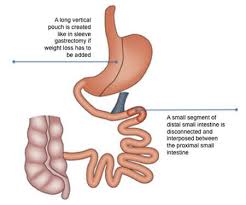

Metabolic and bariatric surgery (MBS) involves procedures that alter the digestive system to treat severe obesity and related metabolic conditions like type 2 diabetes, high blood pressure, and sleep apnea, when diet/exercise fail.